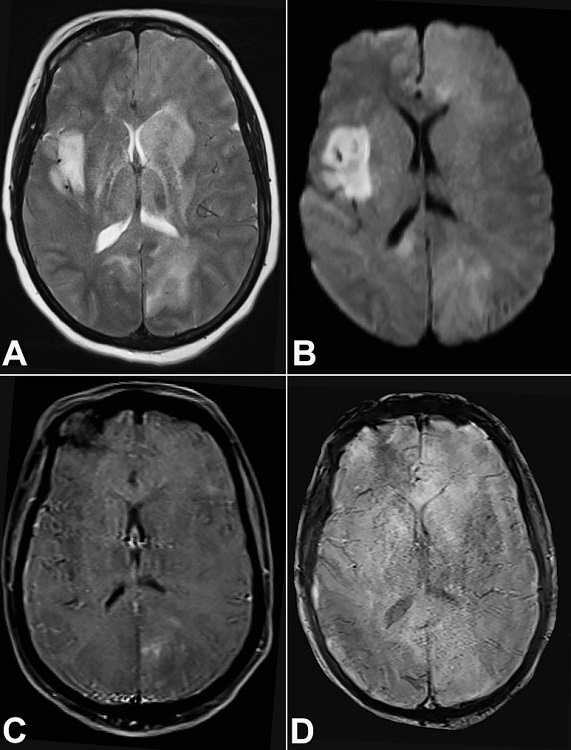

A 48-year-old immunocompetent female patient presented with a subacute (two months history of new-onset seizures) history of generalized seizures followed by right hemiparesis, headache, and vomiting. Her weakness improved completely after she received steroids at an outside center; however, her condition deteriorated rapidly over the next 2 weeks to altered sensorium, and she was referred to our institute for further evaluation. At the presentation, she was stuporous. There was spontaneous eye-opening; however, she was not responding to commands. There was a paucity of movements and hyperreflexia in the right upper and lower limbs, plantar withdrawal response on the right side, and extensor on the left side. The Glasgow coma scale was 10, and the modified Rankin scale was 5. The gadolinium-enhanced magnetic resonance imaging (MRI) of the brain suggested multifocal areas of altered signal intensities involving cortical as well as deep gray matter, subcortical and deep white matter, as well as the corpus callosum, with patchy areas of enhancement, minimal mass effect, and focal areas of diffusion restriction. There was no evidence of hemorrhage (Figures 11D). The HIV serology was negative.

At gross, despite the absence of any mass-like lesions, they produce subtle changes of loss of grey-white distinction, the granularity of the parenchyma, and edema.5 On imaging, primary CNS lymphomas present as homogeneously enhancing periventricular or superficial lesions that are iso to hypodense on CT, iso or hypointense on T1 and hypointense to grey matter on T2.14 Lymphomatosis cerebri, on the other hand, presents as diffuse and asymmetric, abnormal T2-hyperintensity in deep and subcortical white matter with involvement of corpus callosum. Contrast-enhancement pattern may vary from no-enhancement to patchy non-mass-like enhancement or nodular/mass-like enhancement..15 Intravascular lymphoma (IL) is an important differential diagnosis on imaging and may presents with infarct-like lesions, nonspecific diffuse white matter lesions, meningeal enhancement, or large mass-like lesions.16 It needs mention and differentiation from LC; the neoplastic cells in this entity (IL) selectively grow within the lumens of small vessels and capillaries and do not form mass lesions. This pattern is likely caused by a defect in the homing receptors in the neoplastic cells.17 Other differentials include diffuse glioma (gliomatosis cerebri), progressive multifocal leukoencephalopathy (PMLE), vasculitis, microangiopathy, and demyelination.10 The diffuse infiltration of the brain parenchyma evident in gliomatosis Is a potential diagnostic pitfall; however, immunoreactivity for glial fibrillary acidic protein (GFAP) distinguishes the former from the latter. Likewise, the splitting of argyrophilic fibers around the vessels in case of LC and PCNSL, brings vasculitis and microangiopathy amongst the differentials. The neoplastic nature of the infiltrate within the vessels helps in resolving the diagnostic dilemma. Demyelination noted in cases of PMLE typically affects the white matter anywhere within the central nervous system. It is caused due to the JC virus, the inclusions of which are evident in the oligodendrocytes as ground-glass nuclei, and reveals positivity with SV40 immunohistochemistry.18